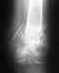

в 2009 году я получила несколько огнестрельных ранений(дробь) и одно ранение в ногу в область коленного сустава и одно ранение в ногу в область коленного сустава и вот на протяжении уже более 4 лет мне не могут помочь срастить перелом перенесла 4 операции по налажению аппарата Илизарова две операции в августе 2009 года и находилась в нем по апрель 2010 года, нога не срослась...местные республиканские врачи( проживаю в Республики Хакасии) сказали,что ни чем не могут помочь, только в 2011 году меня согласились прооперировать в клинике Илизарова в г.Кургане в 2012 году с марта месяца и по 2013 год август я находилась в аппарате илизарова за этот период, было сделано три операции, но результатов положительных это не дало в августе меня выписали с клиники сняли аппарат наложили лангету и выписали с диагнозом имеются ренгенологические признаки консолидации отломков дистального отдела правой бедренной кости,щель коленного сустава дисконгруэнтна так же имеются множественное количество инородных тел дробь..после посещения уже наших врачей они сказали что перелом не срастется совсем и сейчас я нахожусь в лангете, нога все чувствует нет свищей и нет нагноений мышцы не ослаблены я постоянно занимаюсь изометрическими упражнениями...На данный момент были сделаны снимки новые и диагноз несрастающийся перелом ,Помогите нет сил терпеть боль столько лет..прилагаю снимки ..

Ситуация здесь непростая. Стандартное эндопротезирование тут не годится, нужен ревизионный или онкологический протез, да и риск инфекции очень высок. Эндопротезирование коленного сустава делают и в Курганском РНЦ, где Вы уже были. Обсуждали там этот вариант?

Можно обсуждать артродез (замыкание) коленного сустава с остесинтезом длинным внутрикостным стержнем бедро-голень. Сравнительных снмков нет, еще и про укорочение то есть нет информации.

Спасибо что ответили....укорочение после наложения аппарата илизарова есть 5 см...в кургане мне и пытались замкнуть сустав, но консолидации не добились...а вскрывать они боятся...проблема обсуждалась...но я готова пойти на риск пусть лучше заражение и тд чем мучится болями столько лет...возможно у Вас есть информация какие клиники в порядке может эксперимента возьмутся что либо сделать..снимок с отправляла Вам с тех пор по заключению наших врачей при прохождении МСЭК ставят диагноз не сросшийся перелом..может что то посоветуете куда можно обратится.Заранее благодарна.